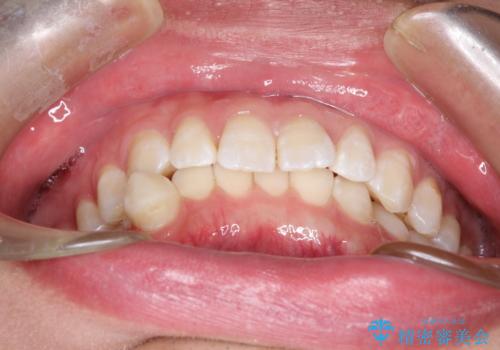

- 前歯がガタガタ、下の犬歯が飛び出ているのを主訴に来院されました。

下の奥歯を後方へ移動させてスペースを確保して、前歯を並べる計画としました。

目立たない装置をご希望されたので、インビザラインにて矯正治療を行いました。

使用時間を守っていただけたので、比較的スムーズに矯正を終了することができました。